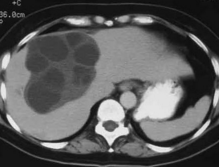

Asymptomatic Hepatomegaly

Navin M. Amin, MD

<div id="article-content-body"> <p><img alt="" src="/sites/default/files/images/Con1WWAmin.jpg" style="border:1px solid black; height:117px;...